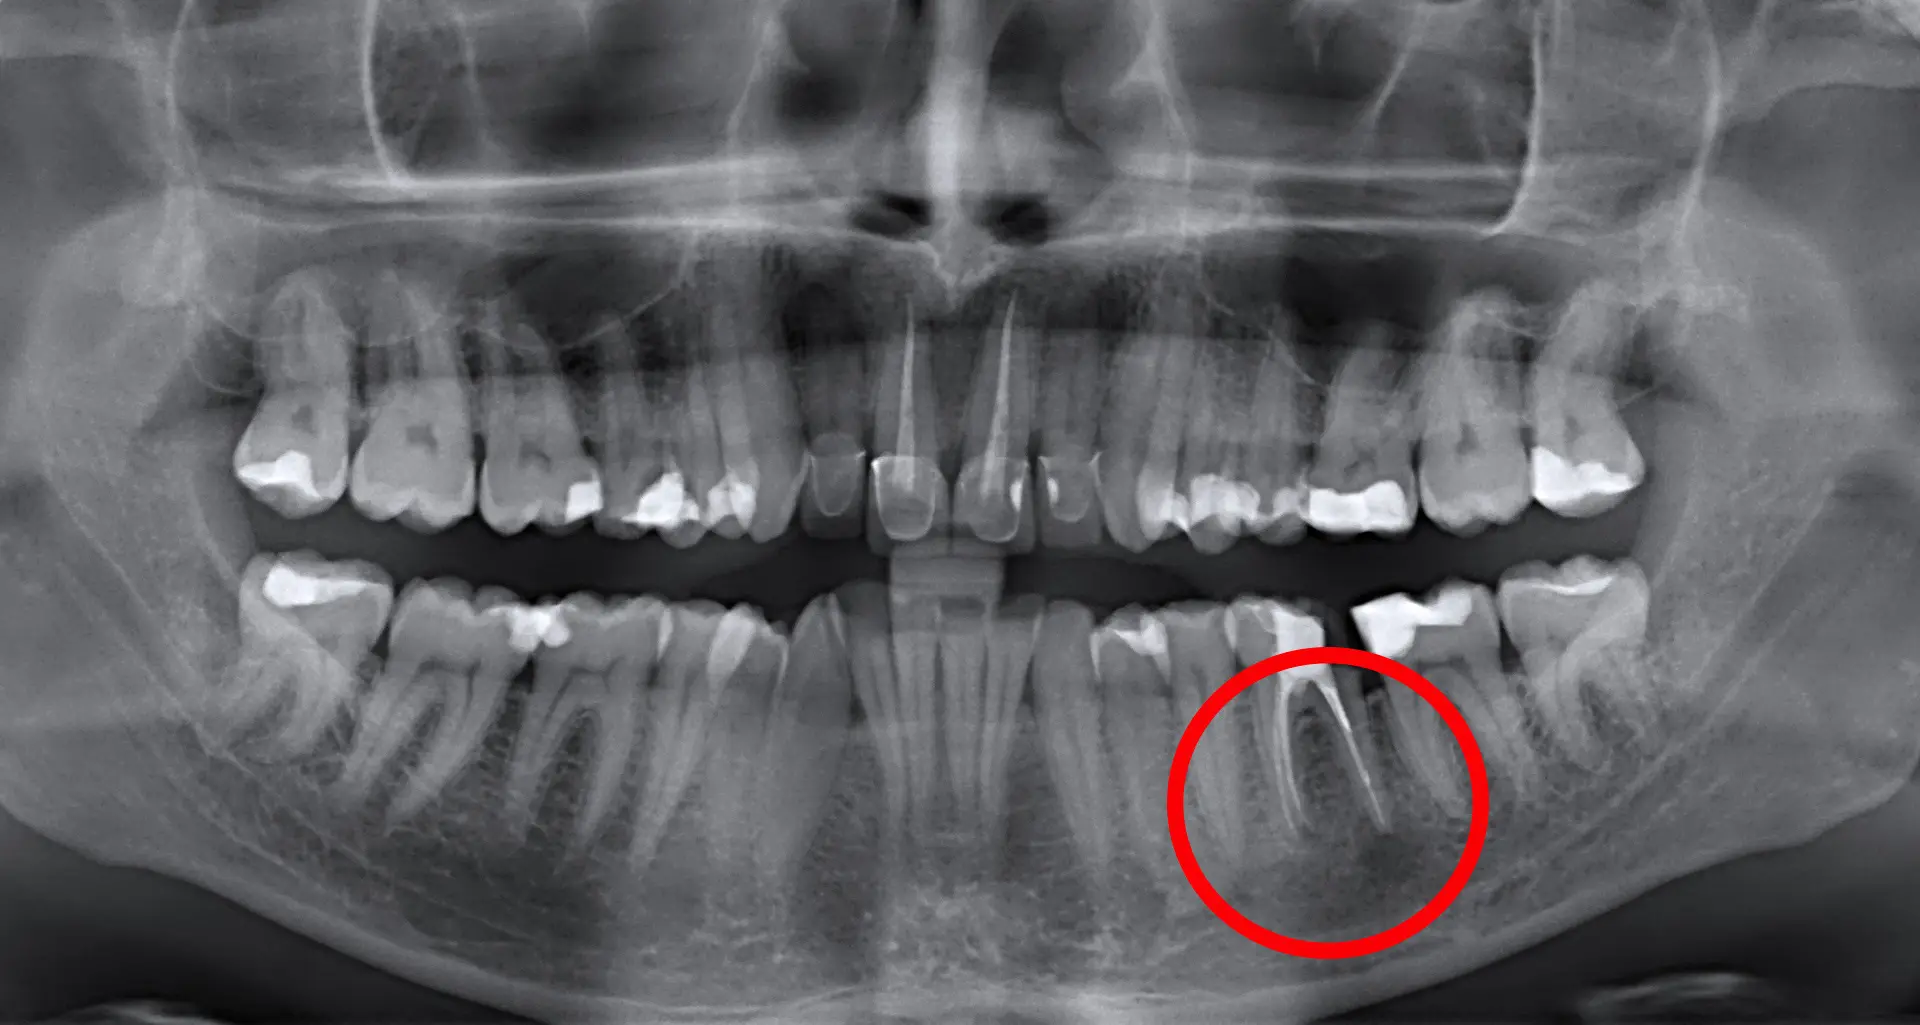

Če občutite bolečino ali otekanje zoba, ki je že endodontsko zdravljen, je potrebno poiskati pomoč stomatologa. Stomatolog bo v tem primeru naredil RTG posnetek tega področja (zoba in okoliške kosti) ter opravil klinični pregled, kakor bi odločil, ali je potrebno opraviti apikotomijo. Koreninski kanali so zelo kompleksni, še posebej na vrhu korenine. Včasih po endodontskem posegu zaostanejo infektivni ostanki znotraj kanala. To lahko privede do kasnejše ponovne okužbe korenine in potrebe za apikotomijo. Pri apikotomiji se odstrani vrh korenine skupaj z vnetnim in inficiranim tkivom, na kar se s polnjenjem kanala zapečati vrh korenine. Apikotomija je danes vse bolj pogost poseg, saj pacientom omogoča ohranjanje zob, katere ni možno zdraviti z endodontsko terapijo in katere bi drugače morali izpuliti. Šteje se za majehn kirurški poseg, traja pa od 30 do 60 minut, odvisno od tega za katero regijo in zob se gre. Posegi na sprednjih zobeh so praviloma krajši, med tem ko so posegi na spodnjih kotnikih najdaljši.